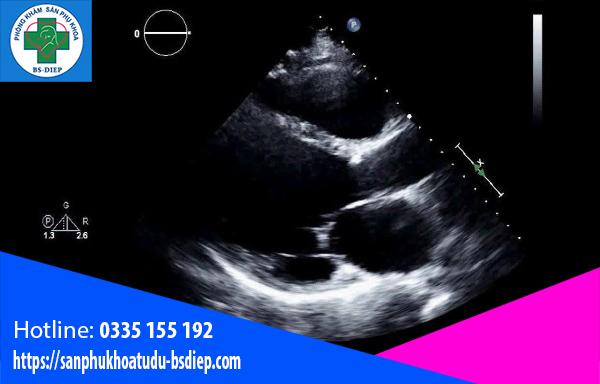

Có thể thực hiện siêu âm nhận định khuyết tật về tim khi nào?

Khi thai nhi được 6 – 9 tuần tuổi, tức ở tam cá nguyệt đầu tiên, mẹ sẽ được siêu âm để kết luận đang có em bé, đếm tuổi thai và kiểm tra tim thai. Cũng nhờ siêu âm để có thể nhận định em bé có bị khuyết tật tim bẩm sinh hay không.

Dù chưa có thuốc hay phương pháp để điều trị khi em bé còn trong tử cung nhưng nhờ vào siêu âm, bác sĩ có thể chẩn đoán và cũng giúp mẹ có thể lựa chọn phương pháp cũng như cơ sở y tế để chăm sóc con sau sinh cho phù hợp.

Siêu âm dị tật

Siêu âm có thể phát hiện những khuyết tật về tim